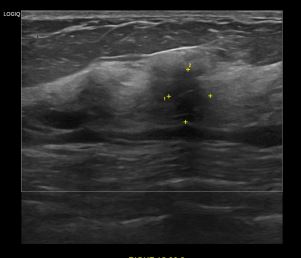

상기환자 외부검사이상으로 정밀검사위해 내원하신 50대 여성분으로

우측유방 혹 총조직검사 시행해 유방암 진단되었습니다.